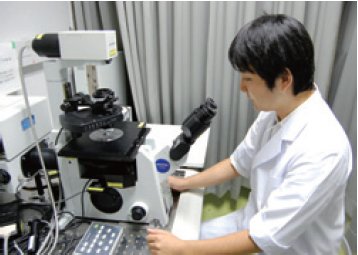

▲光学顕微鏡による心臓組織観察